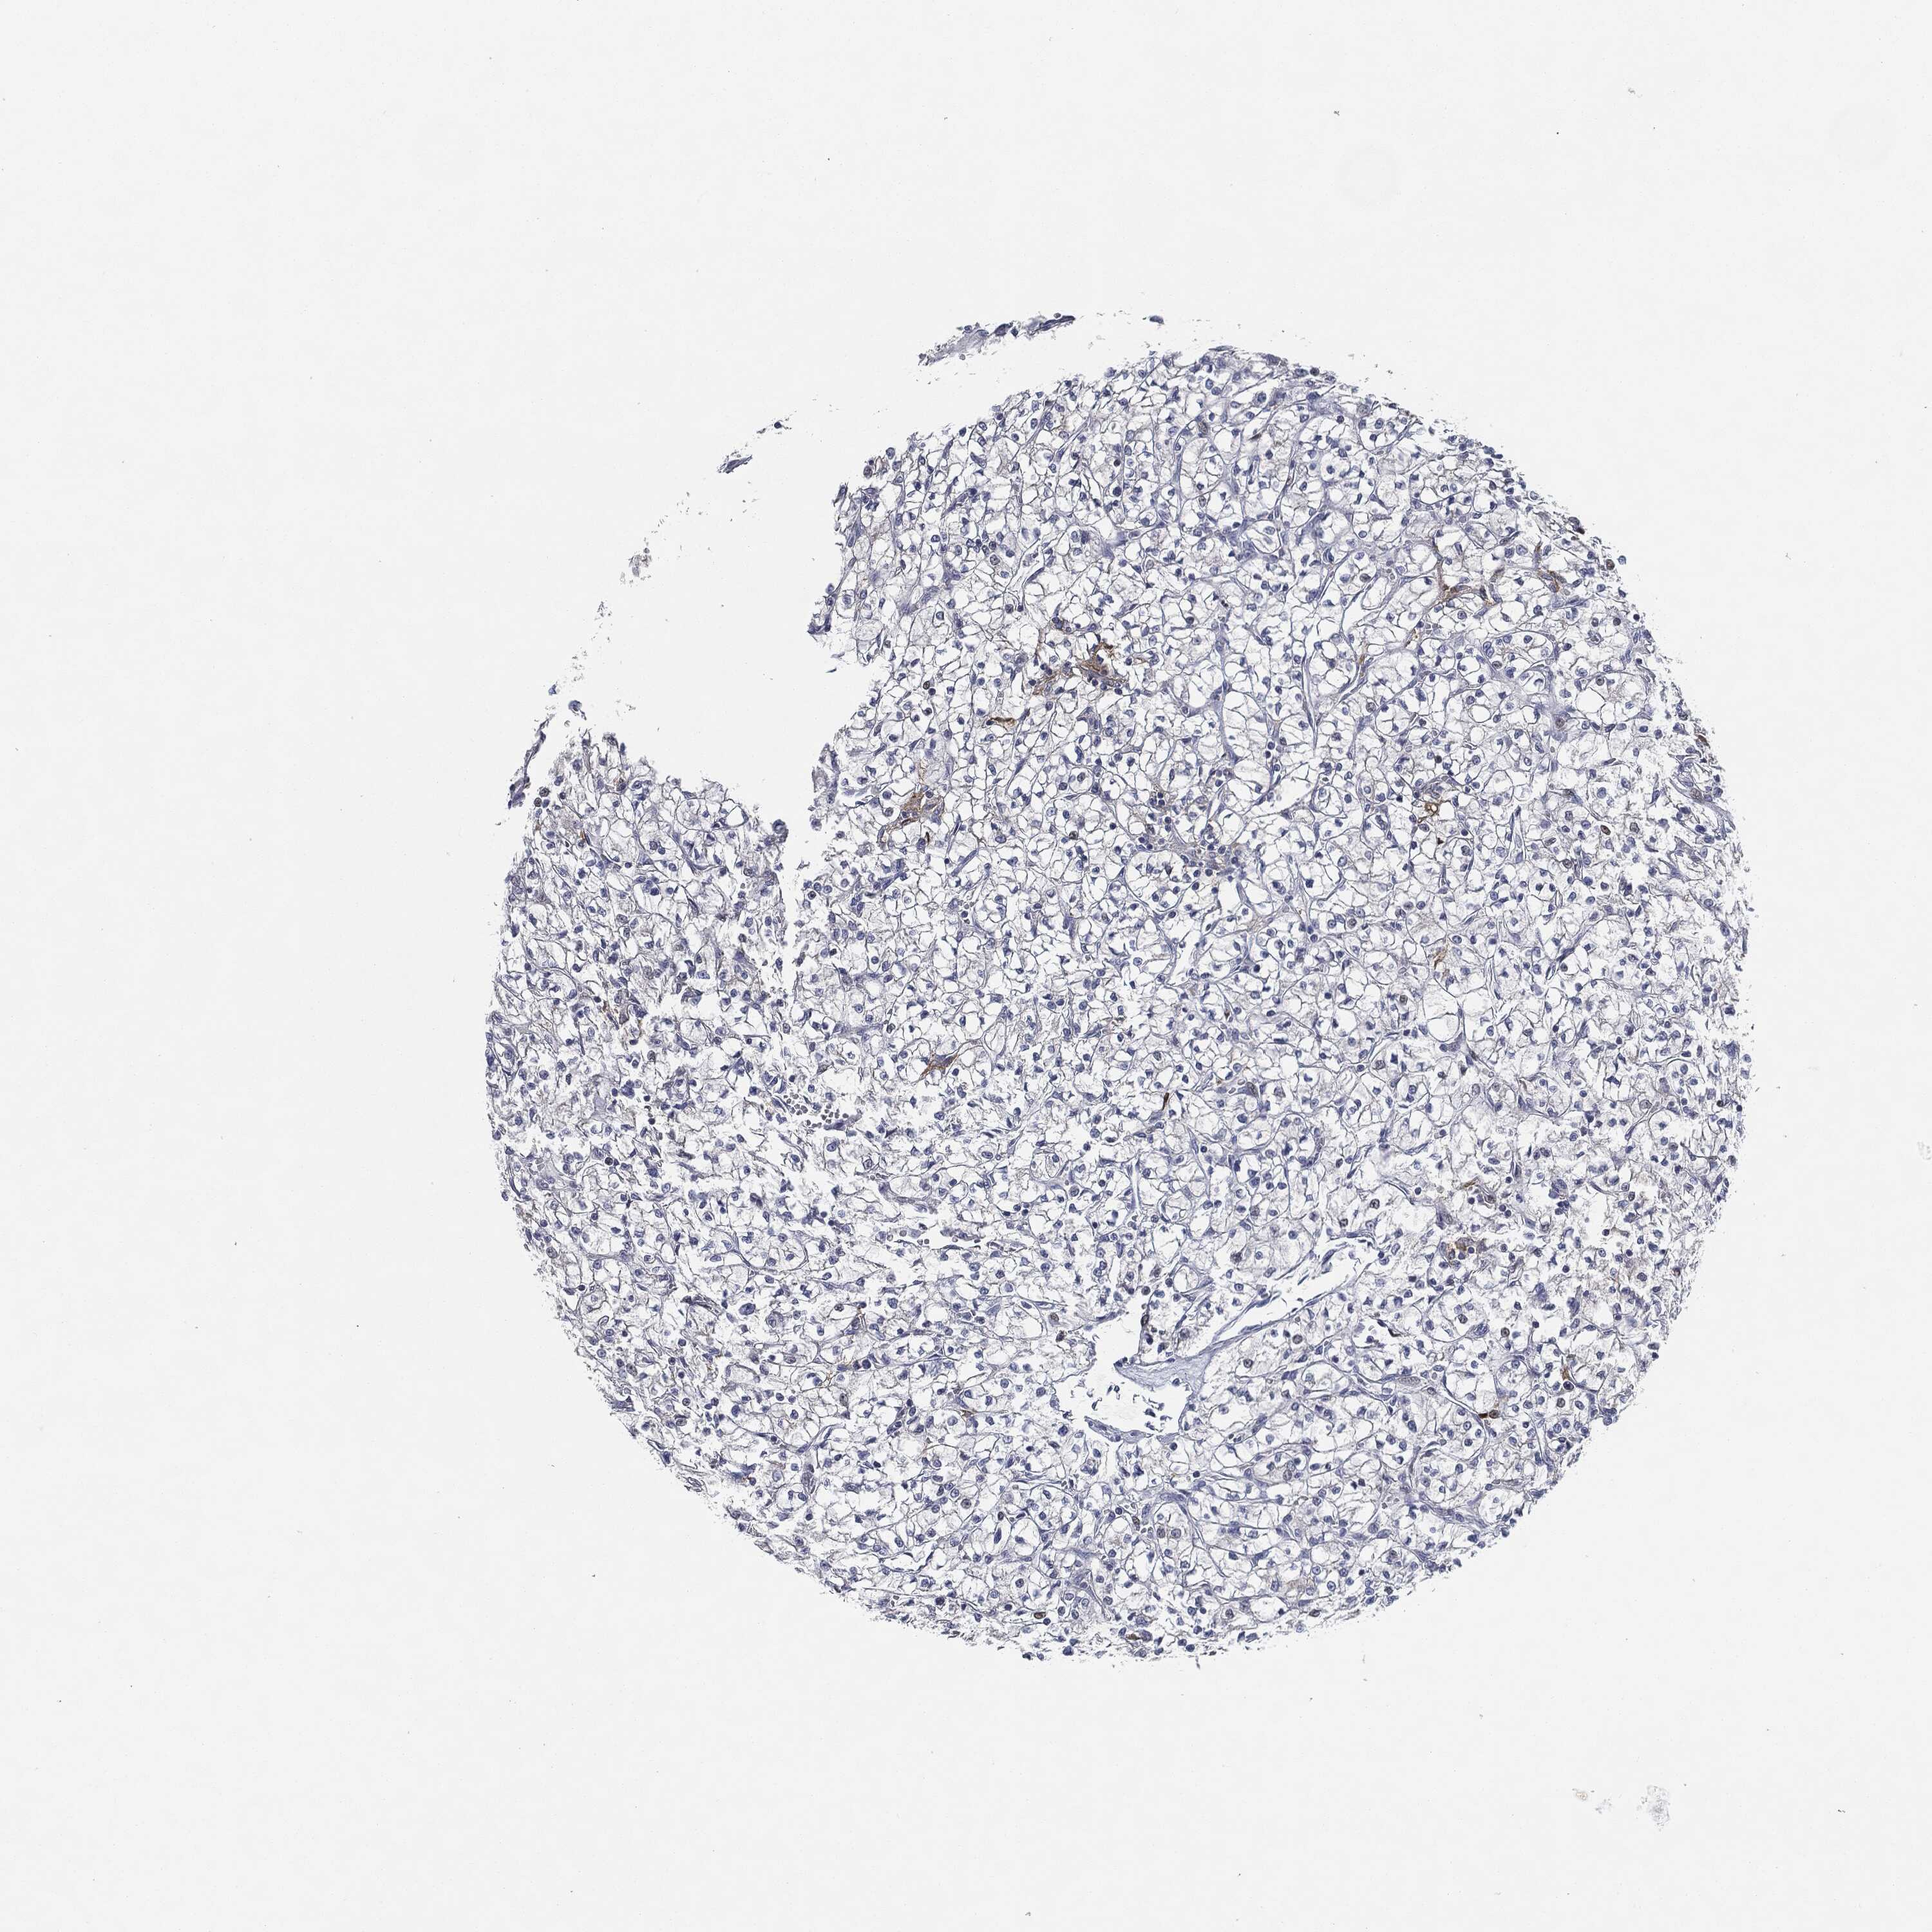

KIDNEY RENAL CLEAR CELL CARCINOMA (VALIDATION) - Interactive survival scatter ploti

The Survival Scatter plot shows the clinical status (i.e. dead or alive) for all individuals in the patient cohort, based on the same data that underlies the corresponding Kaplan-Meier plots. Patients that are alive at last time for follow-up are shown in blue and patients who have died during the study are shown in red.

The x-axis shows the expression levels (FPKM) of the investigated gene in the tumor tissue at the time of diagnosis. The y-axis shows the follow-up time after diagnosis (years). Both axes are complimented with kernel density curves demonstrating the data density over the axes. The top density plot shows the expression levels (FPKM) distribution among dead (red) and alive patients (blue). The right density plot shows the data density of the survived years of dead patients with high and low expression levels respectively, stratified using the cutoff indicated by the vertical dashed line through the Survival Scatter plot. This cutoff is automatically defined based on the FPKM cutoff that minimizes the p-score. The cutoff can be changed by dragging the vertical line or by entering a cutoff value in the square labeled "Current cut-off".

Under the Survival Scatter plot the p-score landscape (black curve; left axis) is shown together with dead median separation (red curve; right axis). Dead median separation is the difference in median mRNA expression between patients who have died with high and low expression, respectively. It is calculated as follows: median FPKM expression of dead patients with high expression - median FPKM expression of dead patients with low expression. This is intended to aid the user in visually exploring custom cutoffs and the associated p-scores and dead median separation.

Individual patient data is displayed and can be filtered by clicking on one or more of the category buttons on the top of the page. Categories describing expression level and patient information include: high, low, alive, dead, female, male and tumor stages. The scale of the x-axis can be toggled between linear and log-scale by clicking on the "x log" button. Mouse-over function shows TCGA ID, patient information and mRNA expression (FPKM) for each patient.

& Survival analysisi

Kaplan-Meier plots summarize results from analysis of correlation between mRNA expression level and patient survival. Patients were divided based on level of expression into one of the two groups "low" (under cut off) or "high" (over cut off). X-axis shows time for survival (years) and y-axis shows the probability of survival, where 1.0 corresponds to 100 percent.

CD274 is not prognostic in Kidney Renal Clear Cell Carcinoma (validation)

: 4.91

Average pTPM 5.0

Number of samples 100